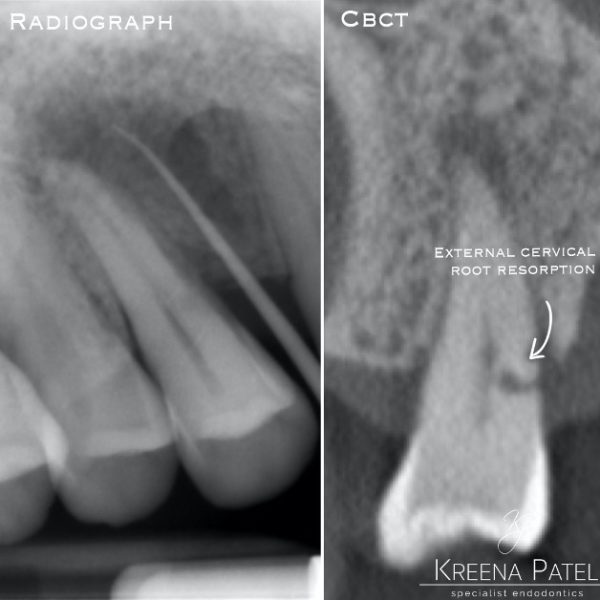

Figure 5: From the PA radiograph LR5 has the classical appearance of internal resorption.

However, the CBCT scan shows the resorption is external cervical resorption.

The resorption starts buccally at the cervical margin. It extends down the root and spreads 360º around the root canal.

We often see this appearance because the canal is surrounded by a protective predentine layer, which is more resistant to resorption